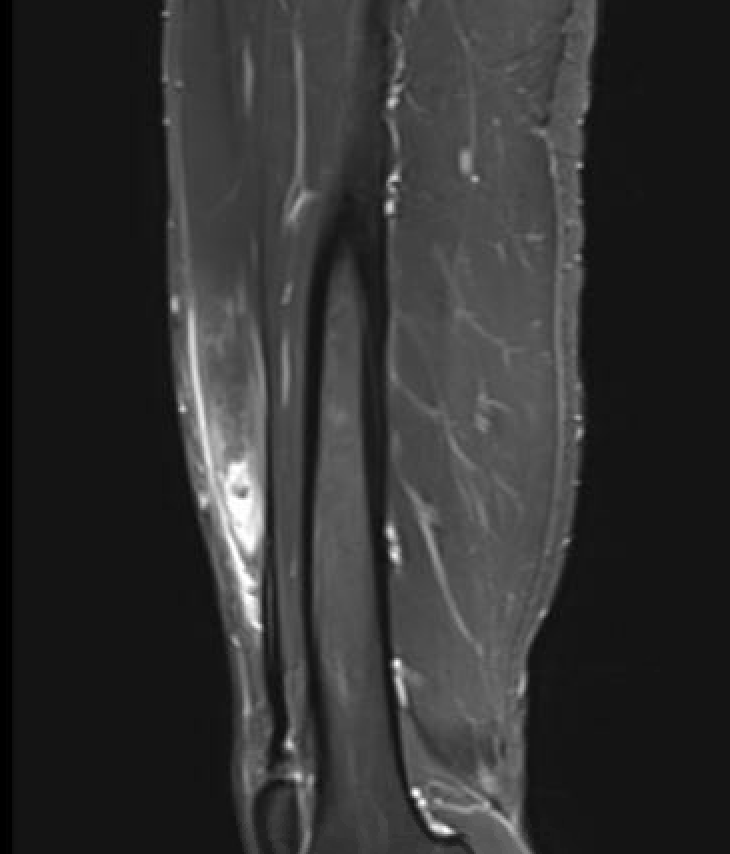

Grade 4C direct head MTPJ rectus femoris